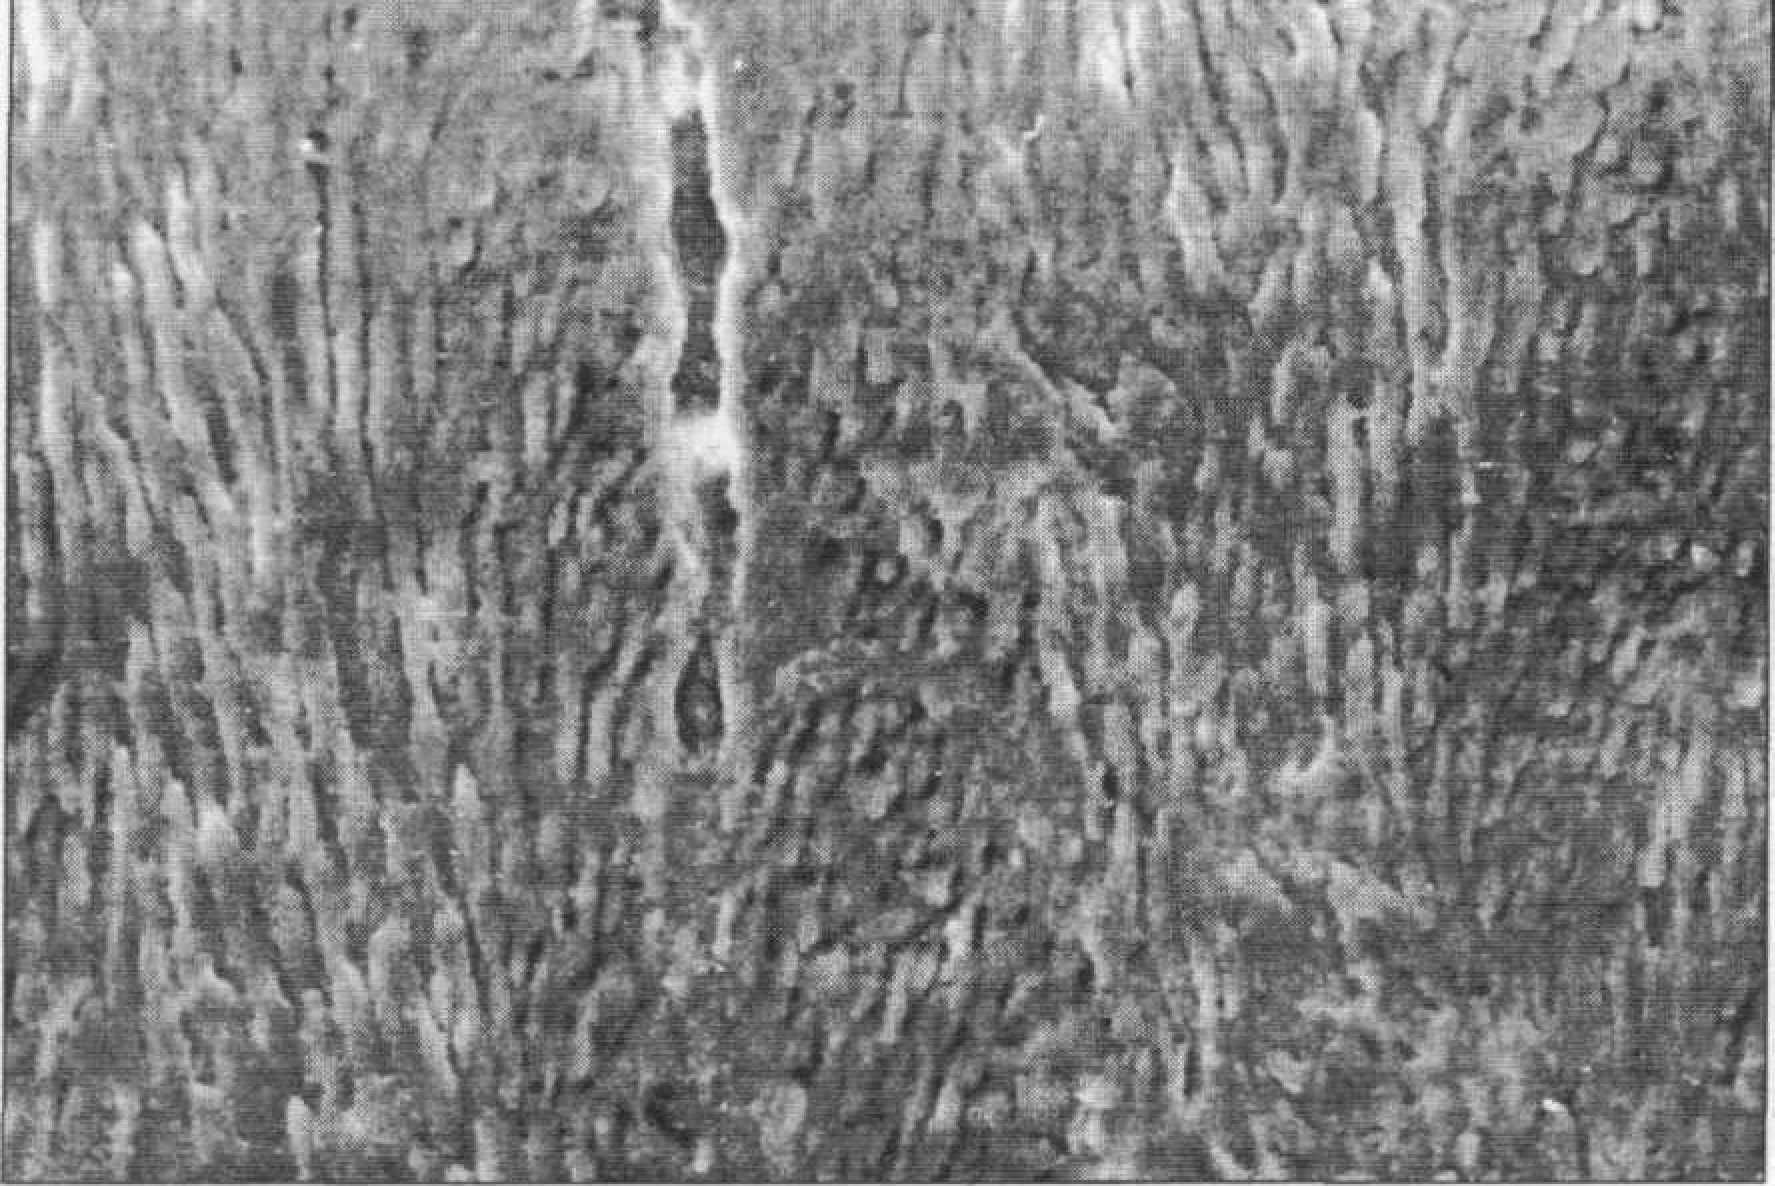

Рис. 103.Головки и тела эмалевых призм. СЭМ. Ув. 1000 Для зубов лиц старших возрастных групп более характерна гомогенизация структур (снижение микропористости), протекающая на различных системных уровнях. Близкая к незрелой эмаль дольше сохраняется в пришеечной области и на проксимальных поверхностях. На шлифах эмали зрелых зубов призмы различаются достаточно четко, имея на поперечном срезе аркадообразую, округлую форму или вид замочной скважины, описанный многими авторами. На продольных шлифах тела и отростки призм формируют широкие и узкие полоски. Они определяются на большей части шлифа, заканчиваясь на поверхности или в подповерхностном слое с узкой беспризменной полоской эмали по периферии. В отличие от детских зубов ближе к поверхности призмы менее контрастны, что объясняется исчезновением ультрамикропор. Крупные микропоры и микрощели встречаются редко. Линии Ретциуса выглядят иначе, чем на эмали незрелых зубов — как «перехваты» или ступени — и значительно менее контрастны (рис. 104).